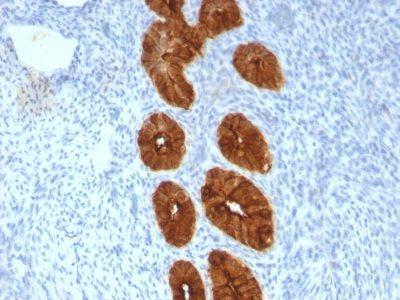

This MAb recognizes full-length MUC1 in a glycosylation-independent manner and can bind to the fully glycosylated protein. The dominant epitope of this MAb is APDTR in the VNTR region. It reacts with the core peptide of the MUC1 protein, which is a member of a family of mucin glycoproteins that are characterized by high carbohydrate content, O-linked oligosaccharides, high molecular weight (>200 kDa) and an amino acid composition rich in serine, threonine, proline and glycine. The core protein contains a domain of 20 amino-acid tandem repeats that functions as multiple epitopes for the MAb. Incomplete glycosylation of some tumor-associated mucins may lead to variable unmasking of the multiple peptide epitopes leading to the observed differences in staining intensity between normal and malignant tissues. This MAb reacts with both normal and malignant epithelia of various tissues including breast and colon.Primary antibodies are available purified, or with a selection of fluorescent CF® Dyes and other labels. CF® Dyes offer exceptional brightness and photostability. Note: Conjugates of blue fluorescent dyes like CF®405S and CF®405M are not recommended for detecting low abundance targets, because blue dyes have lower fluorescence and can give higher non-specific background than other dye colors.

Positive Control

MCF-7 or MDA-231 cells. Breast, colon, ovarian, endometrial carcinoma.

IHC, FFPE (verified), WB (verified)

IHC (FFPE) (verified)|WB (verified)

Immunohistology formalin-paraffin 0.25-0.5 ug/mL|Staining of formalin-fixed tissues requires boiling tissue sections in 10 mM citrate buffer, pH 6.0, for 10-20 min followed by cooling at RT for 20 minutes|Flow Cytometry 0.5-1 ug/million cells/0.1 mL|Immunofluorescence 1-2 ug/mL|Optimal dilution for a specific application should be determined by user